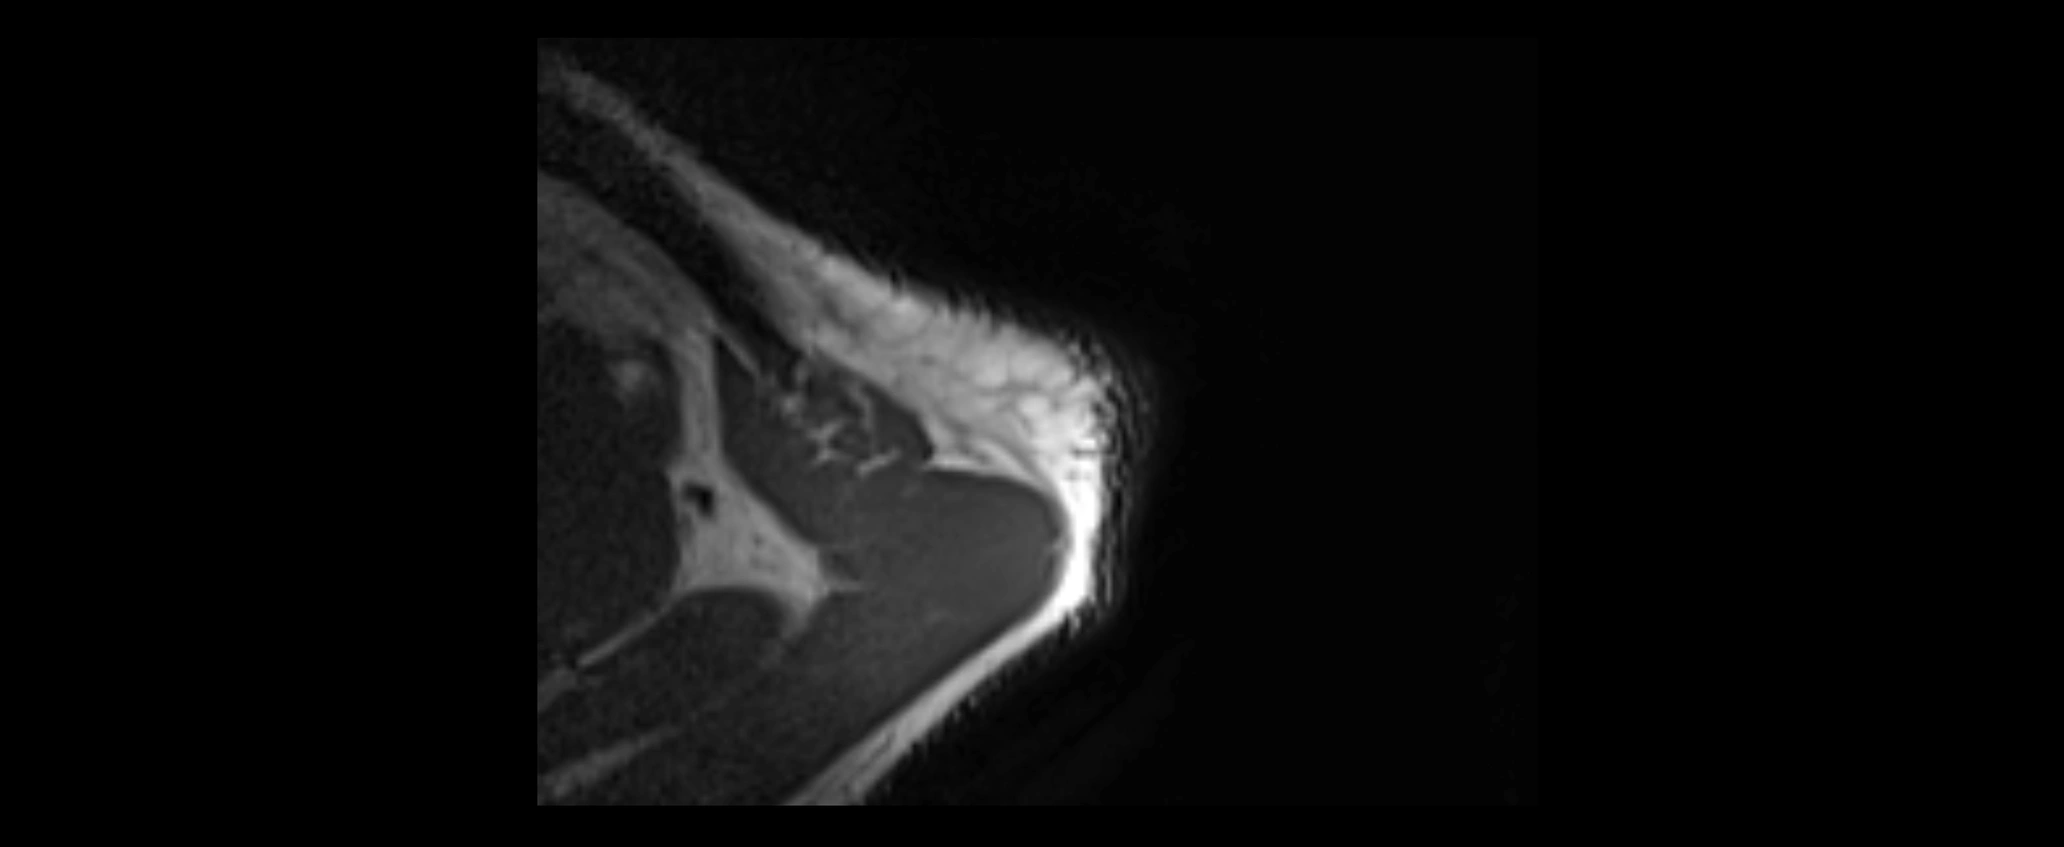

MRI images

image